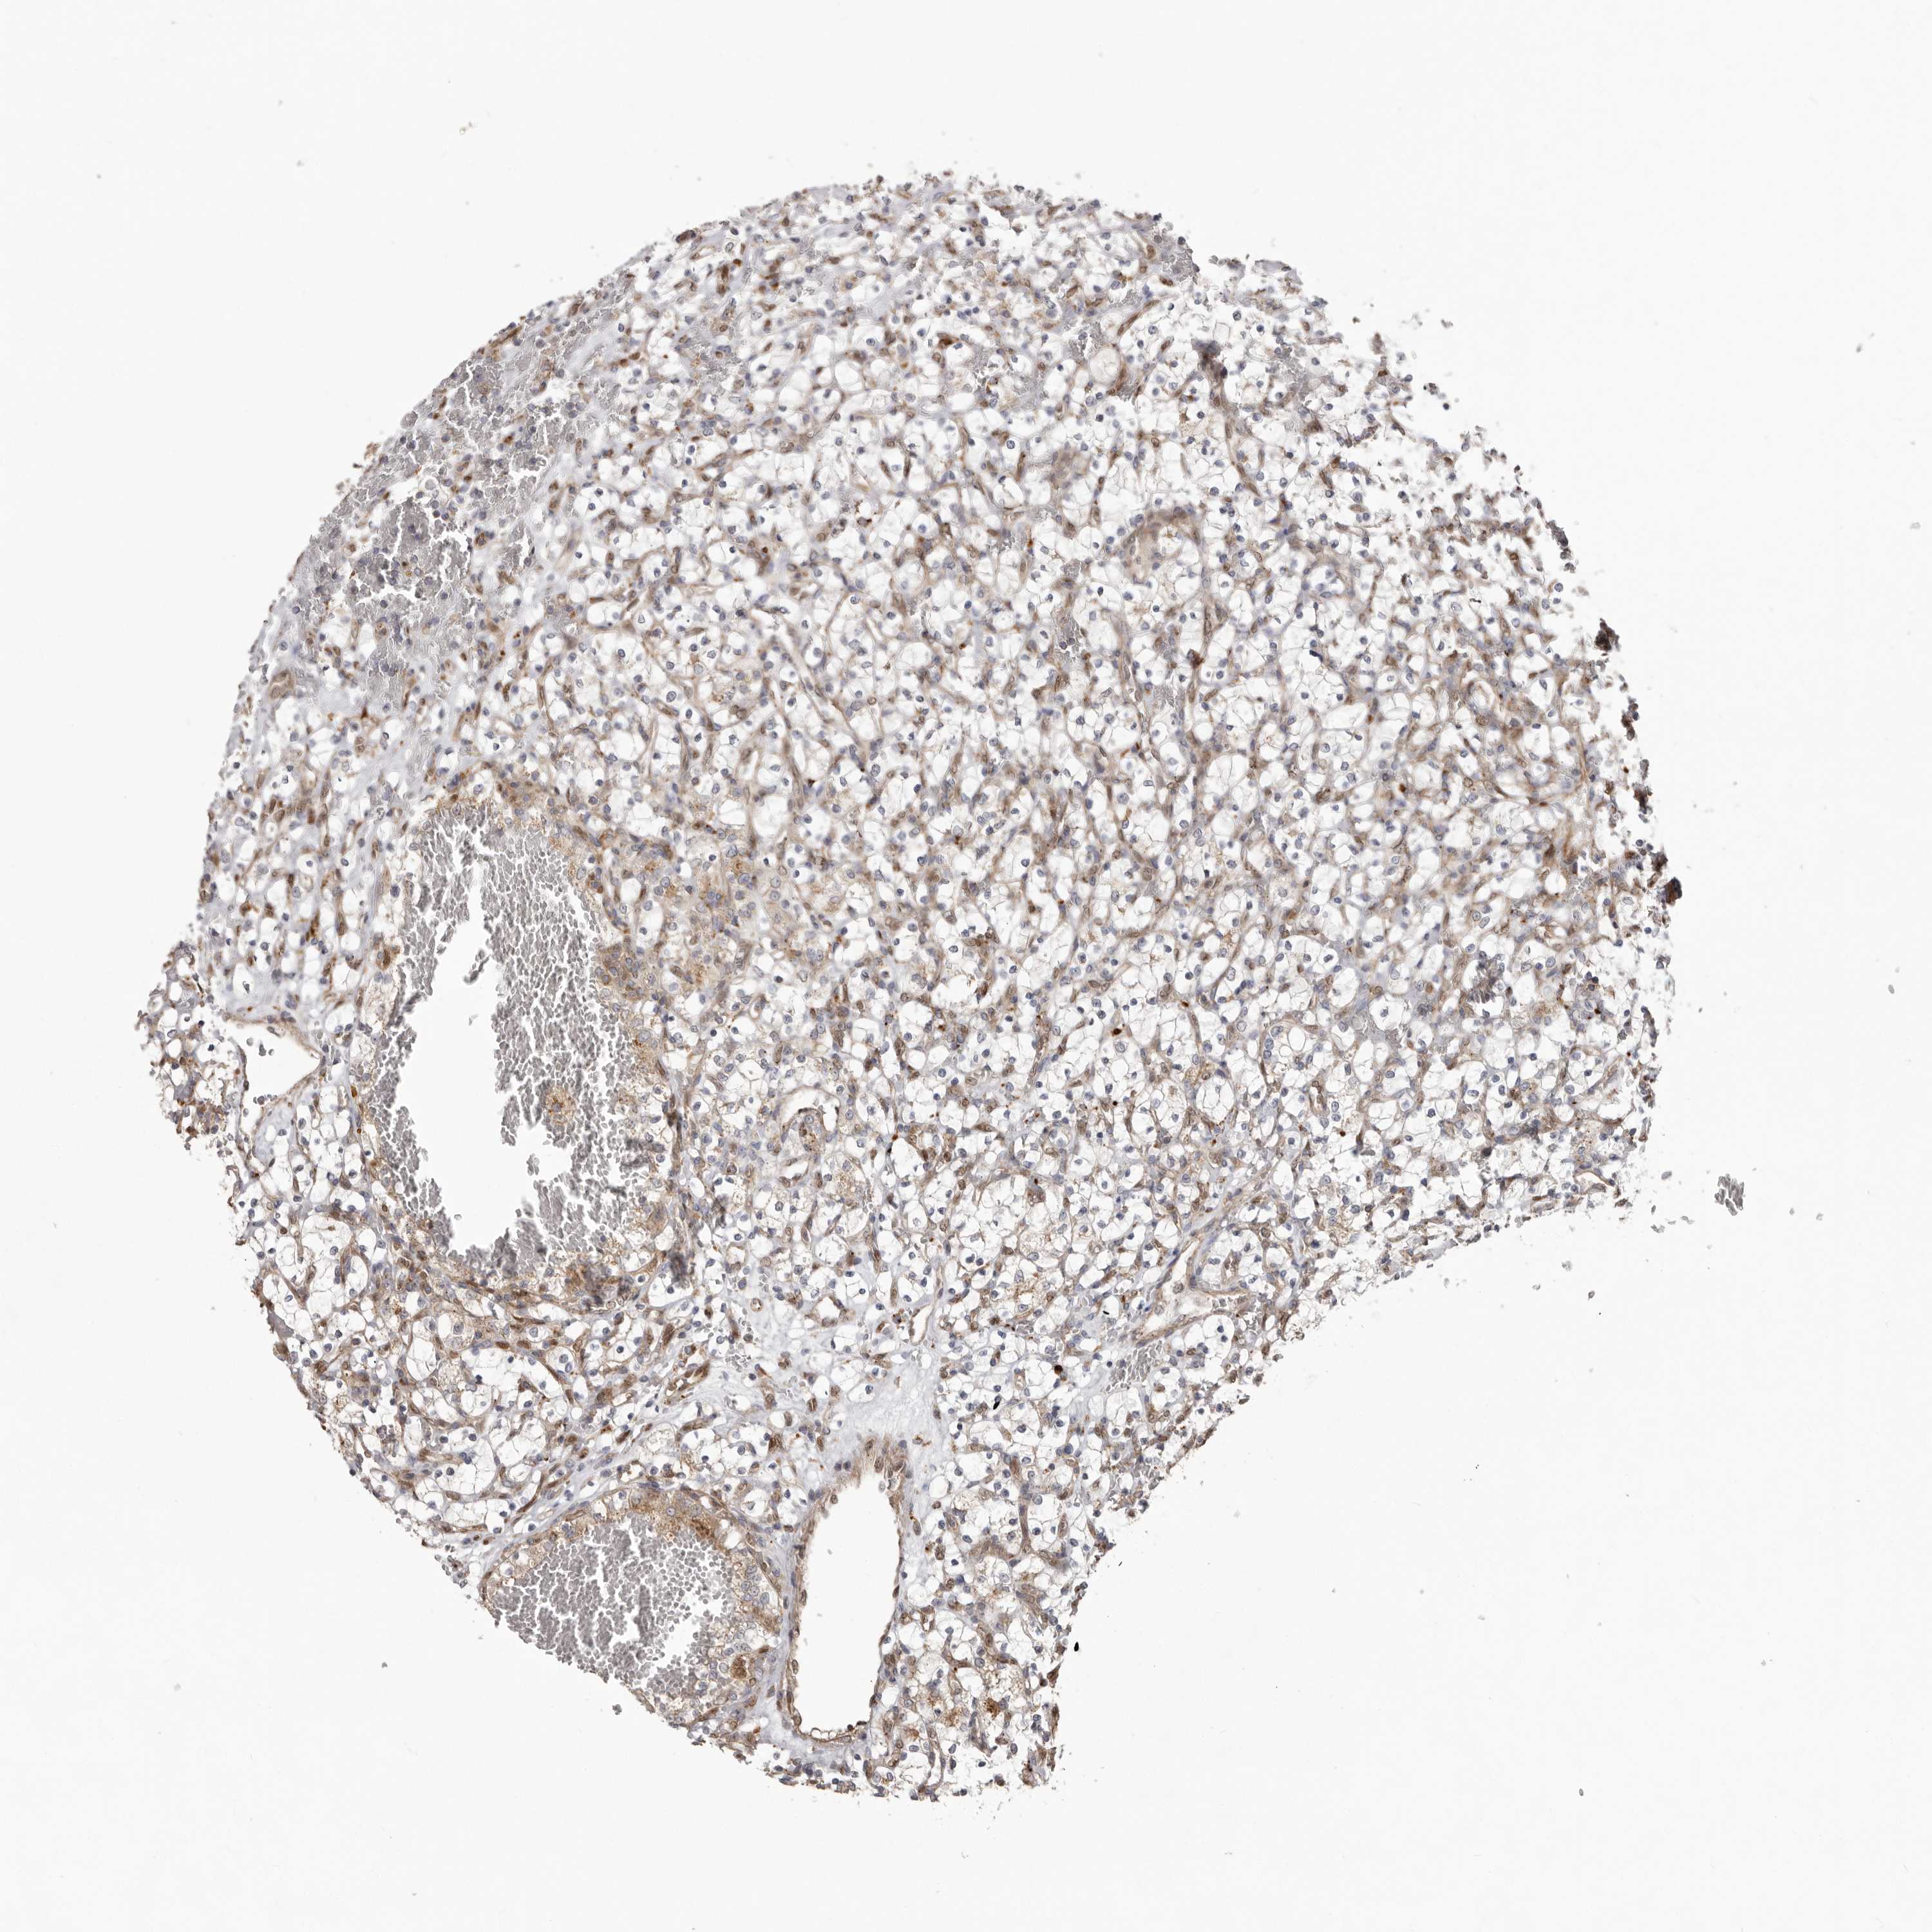

CANCER RENAL CANCER Show tissue menu

KICH TCGA KIRC TCGA KIRC VALIDATION KIRP TCGA PROTEIN RCC CPTAC PROTEIN EXPRESSION